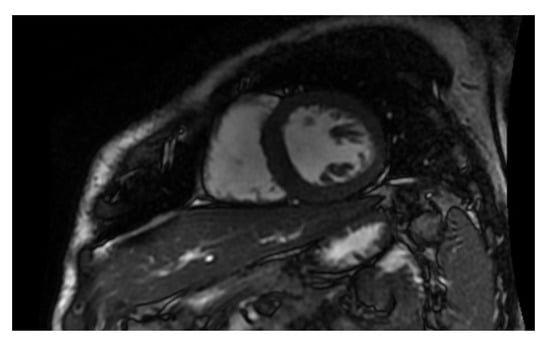

In this protocol, researchers will investigate the potential adverse effects of chest radiotherapy on the heart using the CT scan and MRI (Figure 1 and Figure 2). They will evaluate the coronary vessels and myocardial tissue to determine if and under what circumstances radiation caused heart damage. This information could then be used to develop new follow-up schedules and strategies to ensure that patients are effectively monitored for cardiotoxicity. Other authors have also been investigating the cardiotoxicity of RT using different techniques and protocols. However, the use of MRI is recognized as having its disadvantages, including high cost, long image-acquisition time, and limited availability. Until these challenges can be addressed, its use in cardio-oncologic populations will likely remain limited to those in whom echocardiographic assessments are of poor quality or inconclusive [45,46,47,48,49,50,51,52,53,54].

Figure 2. Cardiac MRI, ventricular short axis.

The use of cardiac MRI has become increasingly popular in clinical practice due to its ability to provide valuable information about anatomical and tissue changes that occur in the heart during pathological conditions [39]. Techniques such as late gadolinium enhancement have become more established, while newer techniques such as T1, T2, and T2 mapping have seen a significant rise in use and development [40]. While there are challenges regarding the practical utilization, accuracy, and reproducibility of cardiac MRI, it has shown higher accuracy and reproducibility than cardiac ultrasound [41]. Cardiac MRI is particularly useful in cases of new cardiac symptoms such as arrhythmias, myocarditis, or reduced ventricular function and can provide valuable diagnostic information for uncommon adverse effects resulting from new anti-tumoral drugs such as immune checkpoint inhibitors [42]. Studies have shown that patients with ICI myocarditis have significantly elevated T1 and T2 values, which have been linked to more pronounced symptoms and lower cardiac function [43]. Additionally, T1 elevation in acute myocarditis may be related to oedema and has independent prognostic value for the development of major adverse cardiac events [44].